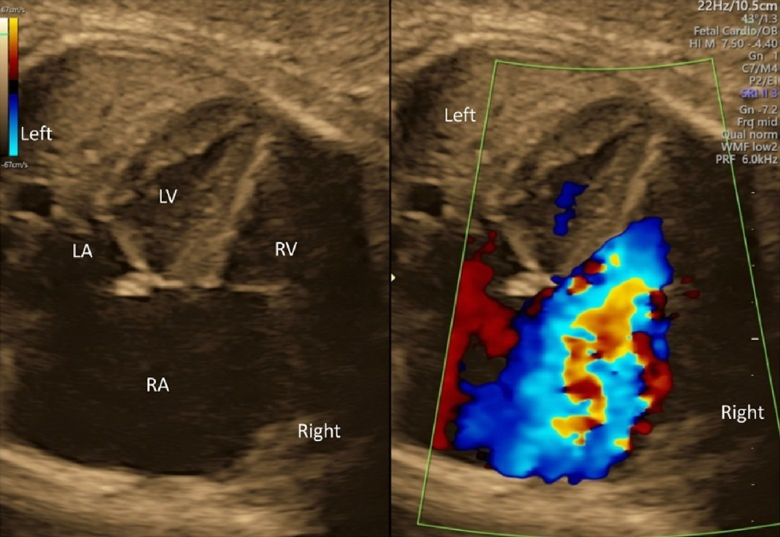

- Whether the AV valves are competent should be determined using color Doppler echocardiography in the 4CV. If moderate to severe AV valve regurgitation were noted, the fetus would likely have structural abnormalities or dysfunction of the heart.

- The direction of the blood flow through the foramen ovale should be assessed using color Doppler echocardiography in the 4CV. Finding a stream from the left to the right, structural abnormalities, such as obstruction within the left heart, should be sought. Finding no blood flow across the inter-atrial septum, premature constriction of the foramen ovale might be the case.